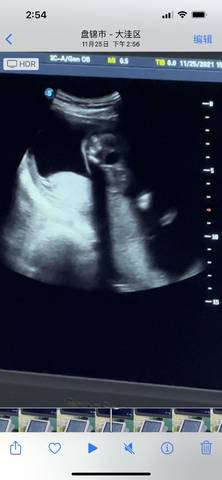

请问我这个是小男孩还是小女孩啊????有没有知道的啊 求告诉 谢谢啦

journal_insert_pic_1677719809journal_insert_pic_1677719813journal_insert_pic_1677719816

你好亲爱的,通过这个来判断男孩女孩是不太准确的哈。那么这个男孩女孩都是我们最爱的宝贝哈,我们要给他同等的关爱和呵护,也祝你可以如愿以偿,心想事成,祝你好运。

#我正在参加,超级妈妈大赛赢奖品 我猜是男宝,也要生后才能确定,宝妈也不要太在乎男女,也是你的宝宝,注意休息!

你好。我们是判断不了男宝宝跟女宝宝的,孕期定期检查,我觉得宝宝健康就好的。祝心想事成 。